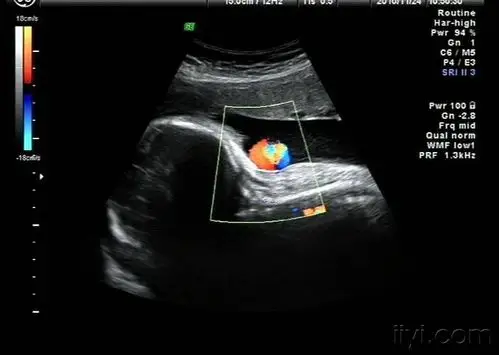

超声诊断脐带缠绕_胎儿

典型脐带绕颈(2周) - 超声医学讨论版 - 爱爱医医学论坛

超声在胎儿颈部观察有无脐带回声,彩色血流观察脐带血流情况.